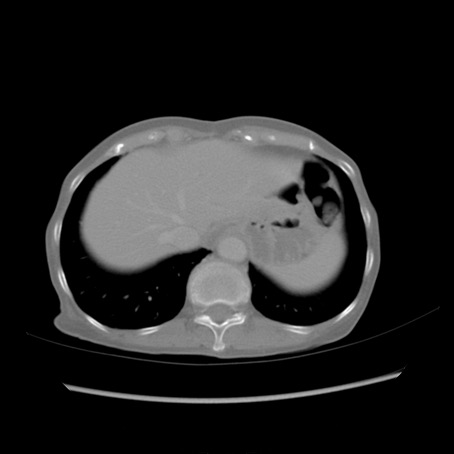

冠状断像

【症例】80歳代女性

【主訴】胸のつかえ感

【現病歴】約9時間前に食後から胸のつかえた感じあり、嘔吐あり、来院。

【既往歴】胃癌(全摘)、胆摘、虫垂炎

【身体所見】心窩部に圧痛あり、反跳痛なし。

【データ】WBC 5700、CRP 0.05